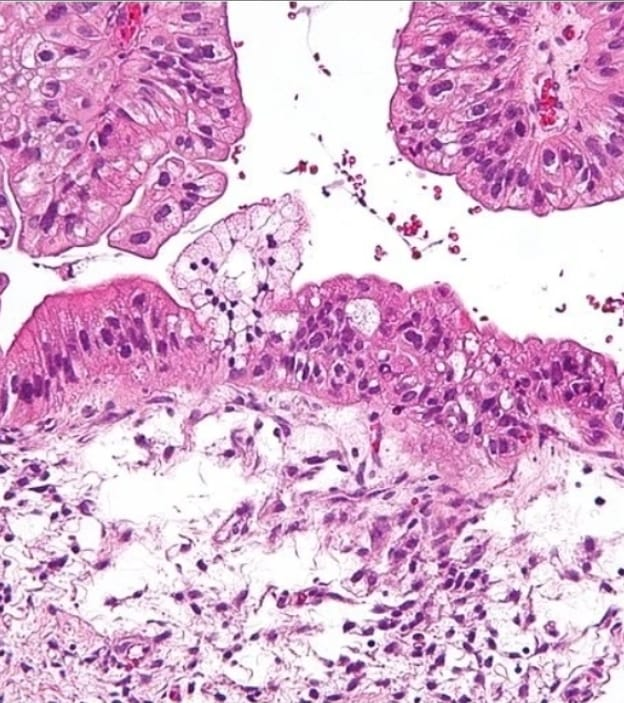

A proposta científica se baseia em um princípio conhecido da biologia tumoral: células cancerígenas produzem energia de maneira diferente das células saudáveis.

Essa alteração metabólica, descrita há quase um século pelo bioquímico alemão Otto Warburg, é considerada uma das marcas fundamentais do câncer e um possível alvo terapêutico.

A equipe desenvolveu uma molécula sintética denominada A14, descrita pelos pesquisadores como uma molécula bio-inteligente. Ela foi projetada para penetrar nas células tumorais e interferir diretamente em suas estruturas energéticas internas, especialmente nas mitocôndrias.

Nas células saudáveis existe um sistema de segurança natural. Quando uma célula apresenta sinais de dano irreversível, uma pequena proteína liberada pela mitocôndria desencadeia um processo de morte celular programada, chamado apoptose.

No câncer, porém, esse mecanismo é bloqueado.

“No tumor, a mitocôndria alterada mantém essa proteína presa entre suas duas membranas, impedindo o gatilho necessário para a apoptose”, explica.

Essa disfunção mitocondrial também está associada a outros processos que favorecem o crescimento tumoral, como a angiogênese — a formação de novos vasos sanguíneos que fornecem oxigênio e nutrientes ao tumor.